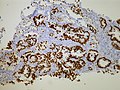

TTF-1 staining in lung adenocarcinoma. (WC) | |

TTF1 in pulmonary adenocarcinoma (WC/Yale Rosen).